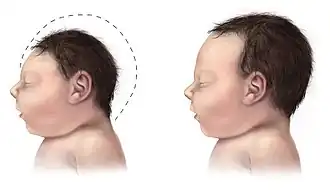

Microcefalia congénita aislada

Los niños con microcefalia nacen con una cabeza de tamaño reducido.[7] Posteriormente, la cabeza deja de crecer mientras que la cara continúa desarrollándose normalmente, lo que produce que el niño tenga la cabeza pequeña, la cara grande, la frente en retroceso y el cuero cabelludo blando y a menudo arrugado. A medida que el niño crece, la pequeñez del cráneo se vuelve más obvia, aunque todo el cuerpo generalmente también presenta peso insuficiente y enanismo[cita requerida]. El desarrollo de las funciones motrices y del habla puede verse afectado. La hiperactividad y el retraso mental son comunes, aunque el grado de cada uno varía. También pueden producirse convulsiones. La capacidad motora puede verse afectada; las afecciones varían de torpeza en algunos casos a cuadriplejia espástica (parálisis).